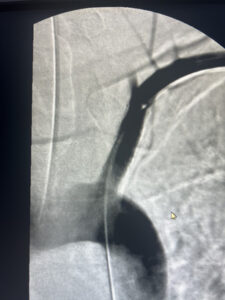

αποκατάσταση με τοποθέτηση stent

σε 24 ώρες εξιτήριο